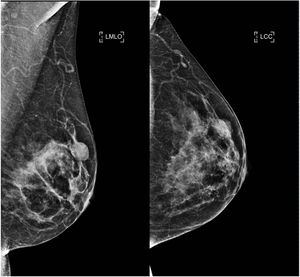

Mammography was performed in nine of the 13 patients studied, with the lesion being visible in six of them. The radiological presentations were: nodule (in five patients) and focal asymmetry (one patient). The nodules were oval, with circumscribed or indistinct and isodense margins, with a mean size of 1.4 cm (range 0.4-2.5). An ACR C (heterogeneously dense) breast density pattern was observed in eight patients. In the remainder, an ACR B pattern (scattered fibroglandular tissue) was observed (Table 2).

Mammographic findings were classified as BI-RADS 2 in three cases, BI-RADS 3 in three cases, BI-RADS 4A in two cases and BI-RADS 5 in one case. In this last case, the classification was determined by a second suspicious lesion that did not correspond to the AME of the breast.

On mammography, AME has been described as a dense, generally circumscribed, round or lobulated mass, sometimes with partially defined margins. Calcifications are not typical findings,2 which is consistent with our series, where most of the lesions were circumscribed nodules and there was only one case of focal asymmetry (Fig. 3). It is important to note that the AME was not visible on mammography in three cases, probably due to tissue overlap in the context of dense breasts.